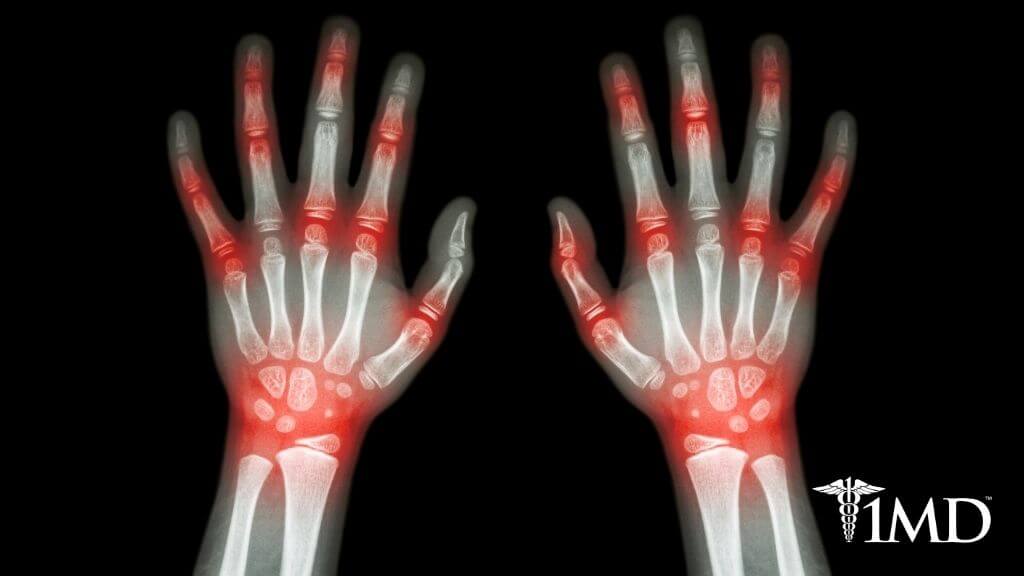

Arthritis affects millions every year and is responsible for putting the ultimate dampener on daily activities and favorite pastimes. Many people are so burdened with joint pain and immobility that they lose the desire and ability to do what they love.

With there being no real cure for arthritis, many feel as though there is no solution but to walk away from their hobbies and joy. But this is a big mistake.